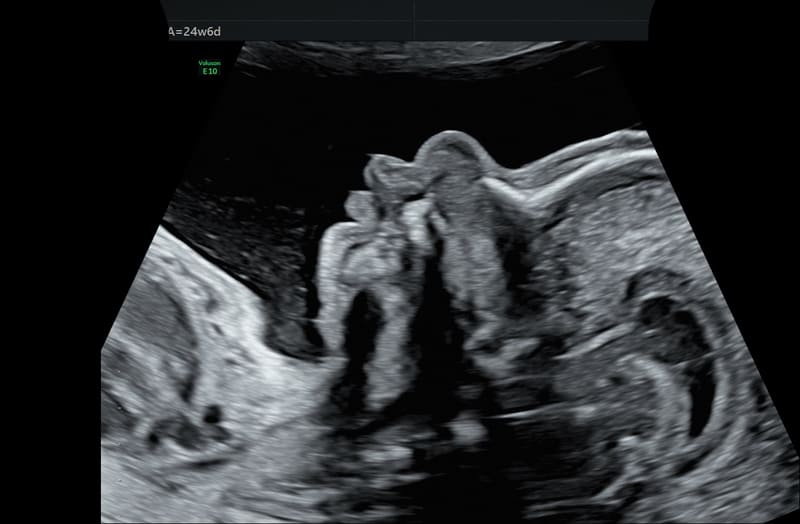

SonoCNS: tool semiautomatico per allineare e visualizzare correttamente le scansioni consigliate nei piani TV (trans-ventricolare), TT (trans-talamico), TC (trans-cerebellare), unitamente alle misurazioni del cervello fetale, utilizzando la tecnologia di deep learning GE Healthcare partendo da un’unica acquisizione 3D.